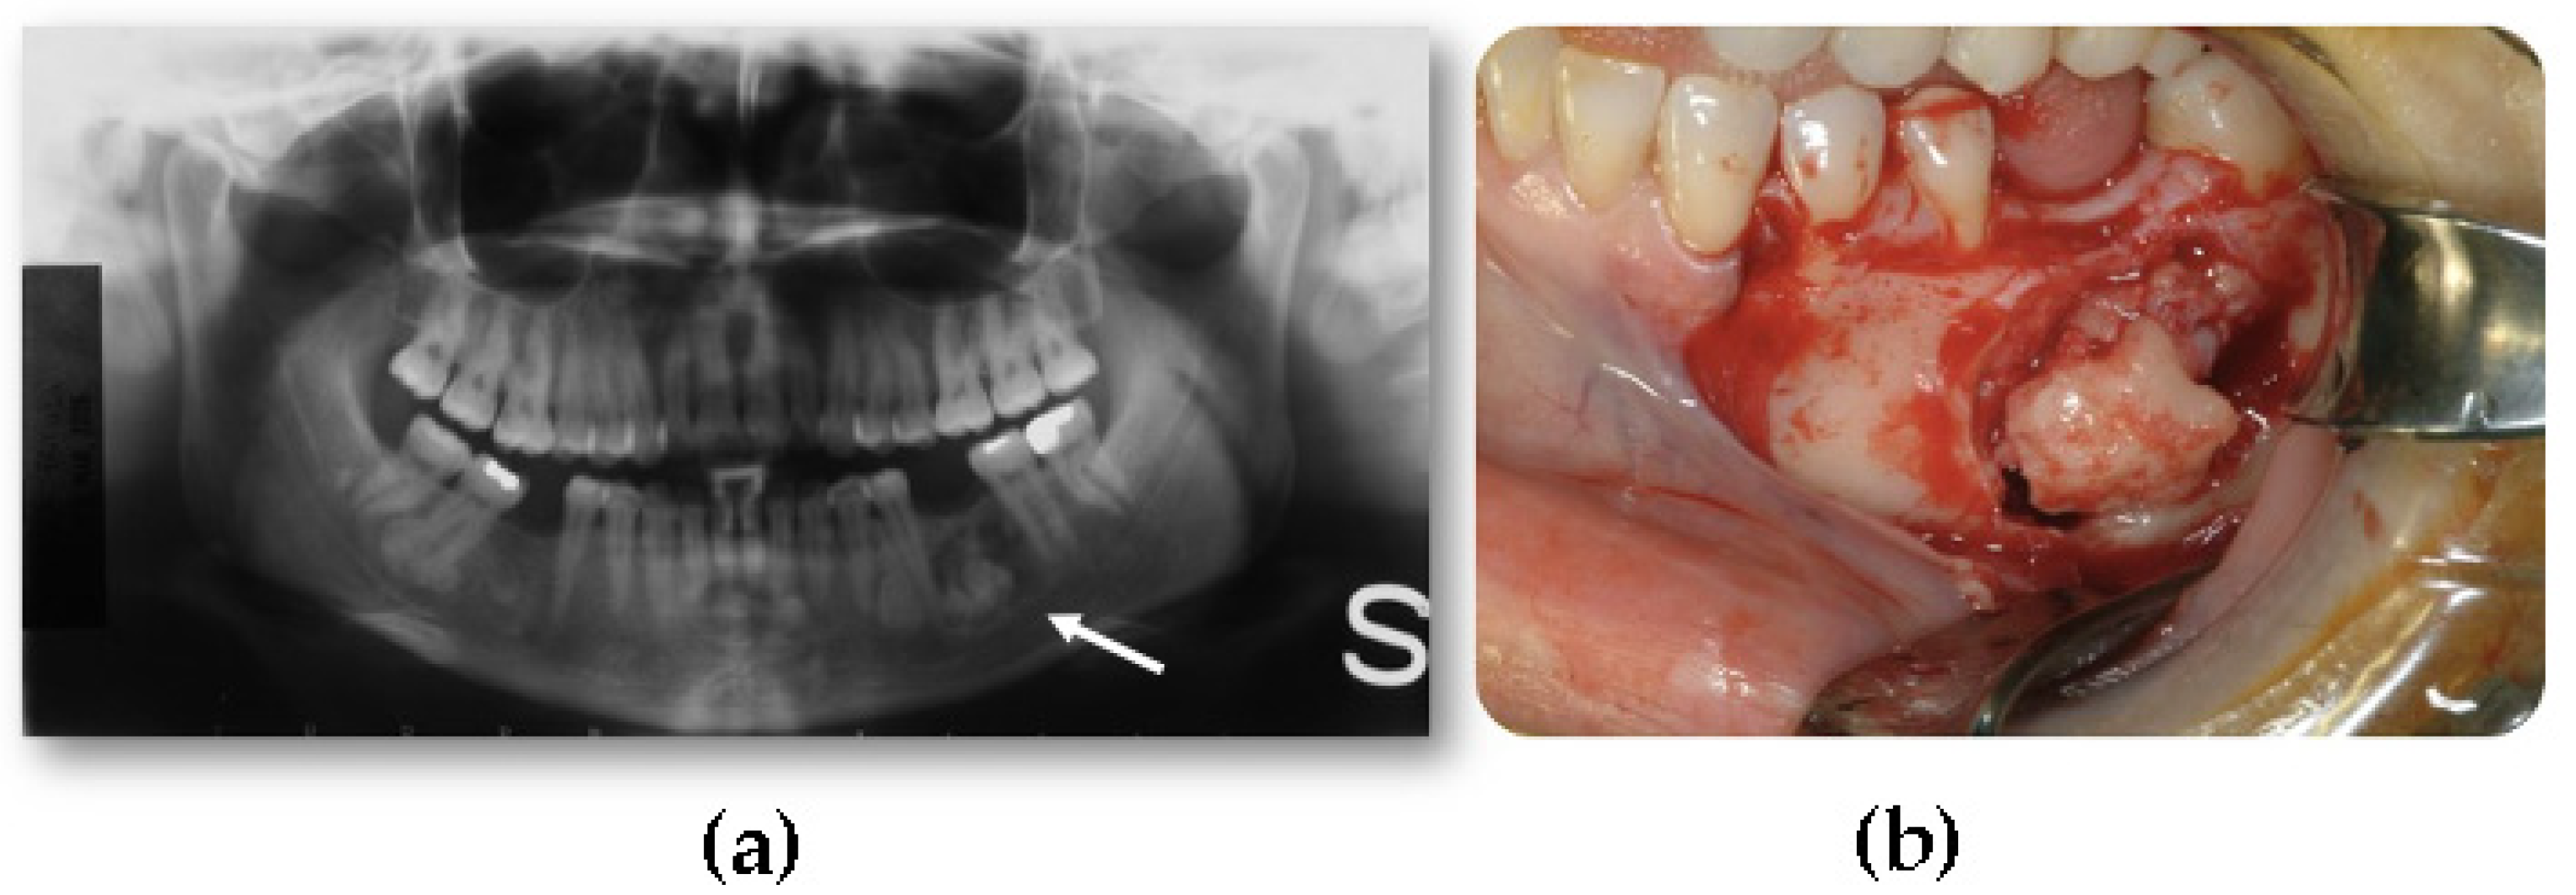

Mandibular traumatic peripheral osteoma a case report Oral Surgery Define Dental Osteoma on a ct scan, an osteoma appears as a very radiodense lesion, similar in appearance to normal bone cortex, and mature osteomas may. osteoid osteoma of the maxilla may present as pain related to dental. an osteoma is a benign bone lesion with no clear pathogenesis, almost exclusive to the craniofacial area. osteomas are benign neoplasm. Define Dental Osteoma.

JCM Free FullText Craniofacial Osteomas From Diagnosis to Therapy Define Dental Osteoma osteoid osteoma of the maxilla may present as pain related to dental. on a ct scan, an osteoma appears as a very radiodense lesion, similar in appearance to normal bone cortex, and mature osteomas may. osteomas are benign neoplasm often associated with facial asymmetry, pain and surface ulceration. an osteoma is a benign bone lesion with. Define Dental Osteoma.

Peripheral osteoma of the mandibular crest a short case study Define Dental Osteoma an osteoma is a benign bone lesion with no clear pathogenesis, almost exclusive to the craniofacial area. osteoid osteoma of the maxilla may present as pain related to dental. on a ct scan, an osteoma appears as a very radiodense lesion, similar in appearance to normal bone cortex, and mature osteomas may. osteomas are benign neoplasm. Define Dental Osteoma.

Mandibular traumatic peripheral osteoma a case report Oral Surgery Define Dental Osteoma an osteoma is a benign bone lesion with no clear pathogenesis, almost exclusive to the craniofacial area. on a ct scan, an osteoma appears as a very radiodense lesion, similar in appearance to normal bone cortex, and mature osteomas may. osteomas are benign neoplasm often associated with facial asymmetry, pain and surface ulceration. osteoid osteoma of. Define Dental Osteoma.

Mandibular traumatic peripheral osteoma a case report Oral Surgery Define Dental Osteoma osteomas are benign neoplasm often associated with facial asymmetry, pain and surface ulceration. osteoid osteoma of the maxilla may present as pain related to dental. on a ct scan, an osteoma appears as a very radiodense lesion, similar in appearance to normal bone cortex, and mature osteomas may. an osteoma is a benign bone lesion with. Define Dental Osteoma.